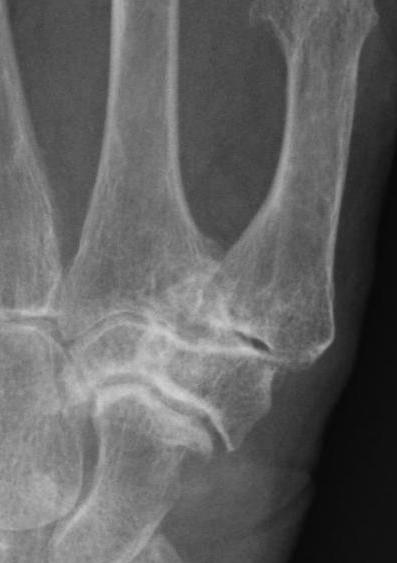

Eaton Classification

| Stage I | Stage II | Stage III | Stage IV |

|---|---|---|---|

|

Xray normal Synovitis |

Joint space narrowed Mild subluxation |

Severe joint space OA Radial subluxation of joint |

CMC + STT OA |